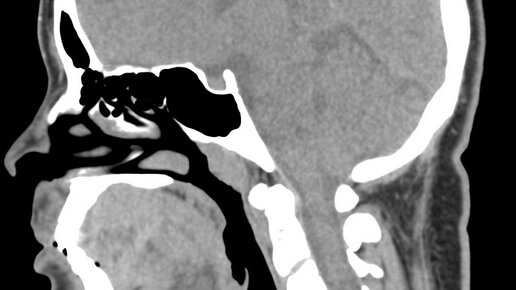

КТ головного мозга (полное название - мультиспиральная компьютерная томография головного мозга) - это неинвазивное, рентгенологическое сканирование костных и мягких структур головы. В процессе обследования компьютерный томограф хорошо визуализирует черепные пластины и мозговые доли...

Для обследования костных структур и отделов мозга ваш лечащий врач может назначить проведение компьютерной томографии головного мозга (она же КТ головного мозга). В ходе данной диагностики происходит рентгенологическое компьютерное сканирование, в процессе которого томограф выполняет послойные снимки обследуемой области, а компьютер объединяет их в трехмерную модель. Таким способом с высокой точностью можно определить последствия травм, наличие и местоположение очагов кровоизлияния и опухолей...